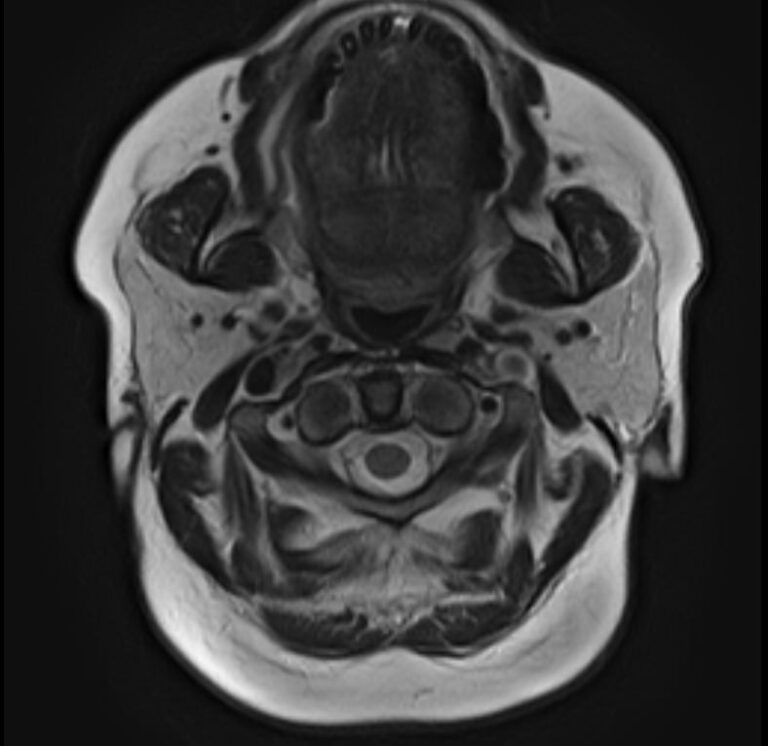

Магнитно-резонансная томография на сегодняшний день является наиболее информативным исследованием слюнных желез. Метод позволяет получить изображения мягкотканных структур с высокой детализацией, при этом отсутствие вредного ионизирующего излучения обеспечивает безопасность процедуры и позволяет проводить ее неоднократно по мере необходимости. Это бывает важно для оценки эффективности проводимого лечения.

В нашей клинике МРТ слюнных желез выполняется на высокопольном томографе экспертного класса TOSHIBA VANTAGE TITAN 1,5 Тесла. Аппарат производит сканирование в трех различных плоскостях в виде тончайших послойных срезов с шагом от 1 мм. Высокая индукция магнитного поля, используемая в аппарате, обеспечивает превосходное качество изображений. Кроме того, с помощью инновационных компьютерных приложений реконструируются объемные изображения исследуемой зоны, что улучшает визуализацию и повышает точность и достоверность диагностики.